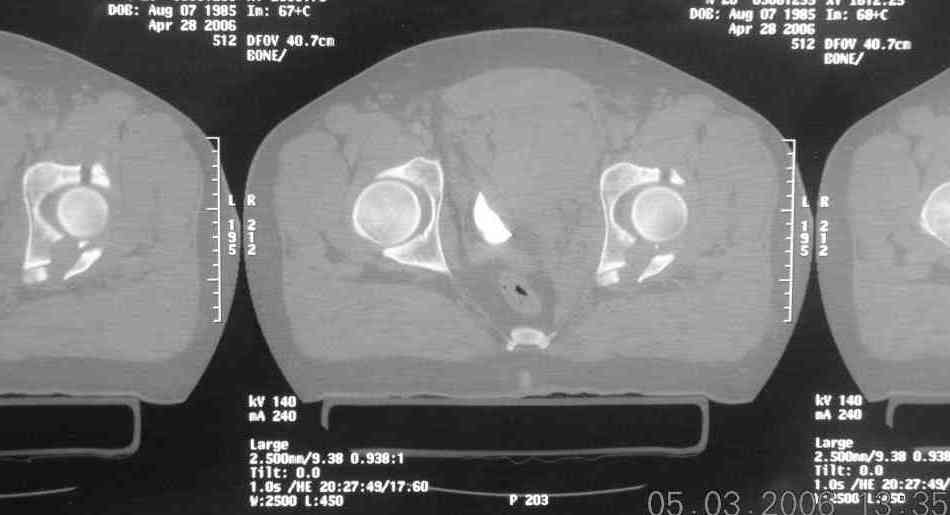

I'll include a few images of a similar injury in a similarly large male patient. This patient "showed up" in our ER c/o hip pain 2 months after being treated in the lateral position, without a quality reduction, without an anterior column transverse supporting implant, with an unbalanced plate applied too medially, with insufficient caudal segment fixation...it took over 8 hours and a 3+ l blood loss to debride the callus from front then

back, excise the HO, release his sciatic nerve, reduce the head-transverse-wall, and fix it...and now it's a staging procedure.

The 2nd example is of a motorcyclist with a transverse fracture-dislocation...he had a closed attempted reduction and placed in traction but the manipulative reduction was not concentric (not unusual for this injury pattern)...so the traction was adjusted to be just enough to disengage the head from the fracture (12#) until he could be cleared for surgery one day after injury...he was treated "urgently" then with a prone KL, clean the fracture, reduce and clamp it, screw it, support with a balanced plate, close, and enjoy...2-3hours, 400cc EBL, blah, blah, blah..